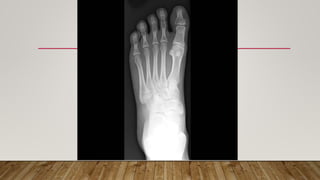

This document discusses radiology and the use of x-rays. It begins with an introduction to radiology and x-rays, noting their importance as the "father of medical investigations." It then discusses anatomy as seen on radiographs and whether x-rays are enough. The document goes on to compare gross views to radiological views, noting what each can and cannot show. It highlights important figures in the development of radiology, from x-rays to CT, MRI, and ultrasound. Specific anatomical structures visible on upper and lower limb x-rays are listed. The document concludes by discussing how pathologies appear on x-rays and the importance of clinical history and knowledge when interpreting radiological images.